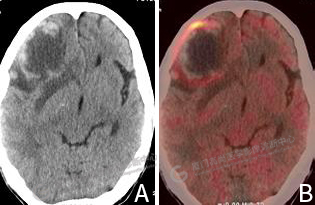

圖2:A CT圖像,右側(cè)額葉見(jiàn)一混雜密度腫塊影,形態(tài)欠規(guī)則,其內(nèi)伴低密度壞死區(qū)。B PET/CT融合圖像,病灶邊緣局限性代謝增高。

雙肺見(jiàn)多發(fā)結(jié)節(jié)影,大者位于左肺下葉外基底段,大小約0.9×0.8cm,F(xiàn)DG攝取明顯增高,SUVmax 7.7。右側(cè)額葉見(jiàn)一混雜密度腫塊影,大小約5.1×4.1cm,形態(tài)欠規(guī)則,其內(nèi)密度不均,伴低密度壞死區(qū),邊緣見(jiàn)斑片、條片狀高密度影,實(shí)質(zhì)部分FDG攝取呈環(huán)形增高,SUVmax 8.3,周圍見(jiàn)片狀水腫帶(圖2)。